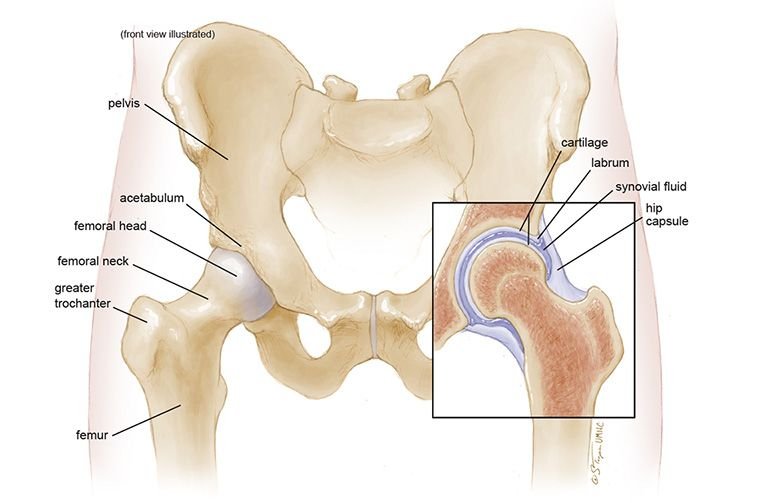

Figure showing hip joint anatomy

Your hip joint connects your upper leg to your pelvis and is made up of the following key components:

- Femur – this is the thigh bone, which forms the “ball” part of the joint

- Pelvis – made up of three bones (ilium, ischium, and pubis) which come together to form the socket

The femoral head (ball) fits into the acetabulum (socket), allowing the joint to move freely. A layer of smooth tissue called articular cartilage lines both the femoral head and the socket. This cartilage helps reduce friction and absorb shock during movement.

Key landmarks of the femur include:

- Femoral neck – the narrowed area beneath the head

- Greater and lesser trochanters – bony prominences that serve as attachment points for major hip muscles

Acetabular labrum

Acetabular labrum – although not a ligament, this cartilage ring plays a major role in keeping the hip joint stable